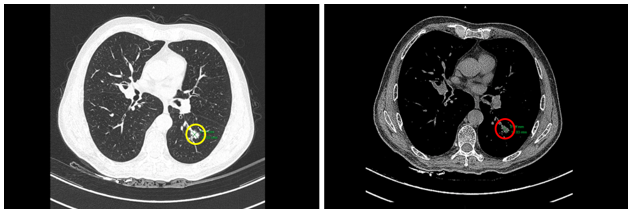

Case lâm sàng: Ứng dụng trí tuệ nhân tạo (Artificial intelligence – AI) trong chẩn đoán và điều trị sớm Ung thư phổi tại Trung tâm Y học hạt nhân và Ung bướu, Bệnh viện Bạch Mai

Theo GLOBOCAN 2022, ung thư phổi đứng đầu về số ca mới mắc (2.480.301 ca mới mắc chiểm 12.4%) và dẫn đầu số ca tử vong (1.817.172 ca tử vong chiếm 18.7%) trên toàn thế giới.  Tại Việt Nam tỷ lệ mắc ung thư phổi xếp thứ ba 13,5% lệ tử vong...